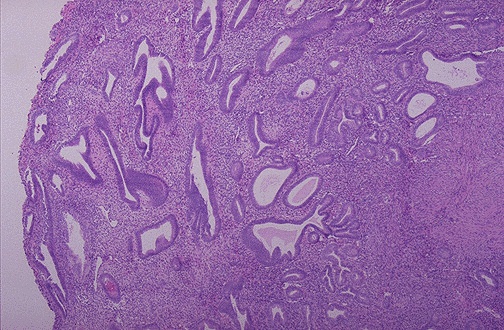

| This is endometrial hyperplasia in which the amount of endometrium is abnormally increased and not cycling as it should. The glands are enlarged and irregular with columnar cells that have some atypia. Simple endometrial hyperplasias can cause bleeding, but are not thought to be premalignant. However, adenomatous hyperplasia is premalignant. |